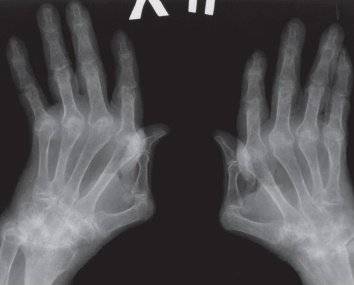

Вторая рентгенологическая стадия заболевания разделяется на две подгруппы, в зависимости от степени повреждений в виде эрозии суставной поверхности:

- подгруппа А второй рентгенологической стадии характеризуется отсутствием эрозий на суставных поверхностях, на снимке выявляют околосуставной остеопороз в виде кист (локальные просветления костных структур), участков костных уплотнений и более заметное сужение щели между суставными поверхностями;

- подгруппа Б второй рентгенологической стадии патологии помимо основных проявлений характеризуется появлением эрозий поверхностей суставов, не более, чем в четырёх местах.

Происходит деформация кистей в виде «плавника моржа» (подвывихи пястно-фаланговых сочленений) или «шеи лебедя» (формирование стойких сгибательных контрактур пястно-фаланговых сочленений и переразгибание межфаланговых суставов), невозможность отведения большого пальца кисти. Больной не может выполнить простейшие манипулятивные действия руками, в том числе испытывает затруднения в удерживании чашки, ложки и так далее.

Кости становятся хрупкими из-за выраженного дегенеративного процесса. Учащаются случаи подвывихов, вывихов, патологических переломов. Заживление повреждений длительное, требует проведения оперативных вмешательств.

Третья степень ревматоидного артрита на рентгене:

- образование единого костного блока в районе мелких суставов кистей;

- более 5 участков эрозии костной ткани;

- сужения суставных щелей мелких и крупных суставов;

- появление остеопорозных кист;

- формирование кальцификатов мягких тканей (ревматоидные узелки), которые на снимке выглядят как участки затемнения округлой формы, диаметром до 2 см в районе мягкотканого компонента вокруг суставов (чаще кисти, локтевые, коленные).